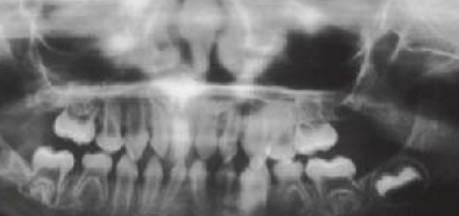

Los dientes supernumerarios surgen como resultado de una geminación de la lámina dental que se produce de forma esporádica o se heredan, como sucede con la displasia cleidocraneal (fig. 9.8).

La forma de los dientes puede recordar a la forma de las piezas normales (diente suplementario), es decir, incisiforme, caniniforme o molariforme; de no ser así, sería cónico o tuberculado.

Habitualmente se presenta como consecuencia del fallo en la erupción de uno o más dientes permanentes y en general presenta formas cónicas o tuberculadas.

Se ha considerado a los dientes supernumerarios como manifestaciones de una dentición separada que se produce entre las denticiones temporal y permanente; de ese modo, se puede predecir cuándo y dónde podrían formarse los dientes supernumerarios (Jensen & Kreiborg 1990).

Diagnóstico

- Erupción fallida o ectópica de un diente permanente (fig. 9.8B).

- Estudio radiológico rutinario.

- Como parte de un síndrome, como la displasia cleidocraneal (fig. 9.9).

Tratamiento

- A menudo erupcionan dientes cónicos que se pueden extraer con mucha facilidad (fig. 9.8A).

- Los dientes tuberculados o cónicos invertidos requieren extracción quirúrgica (fig. 9.8D) tan pronto como sea posible para permitir la erupción sin obstáculos del diente permanente.

- Resulta esencial localizar la posición del diente que debe extraerse antes de la cirugía. Pueden realizarse radiografías periapicales que emplean la técnica del desplazamiento del tubo (tube-shift) para localizar el diente, pero siempre entrañan la posibilidad de errores e interpretaciones erróneas. De la misma manera, pueden utilizarse radiografías panorámicas y oclusales maxilares estándar. La proyección oclusal de vértice permite obtener una muestra más precisa de la localización horizontal y anteroposterior, por lo que es la preferida (fig. 9.8C) para ayudar a determinar el procedimiento quirúrgico óptimo. Algunos centros prefieren no utilizar esta vía debido a una excesiva radiación en el cráneo.